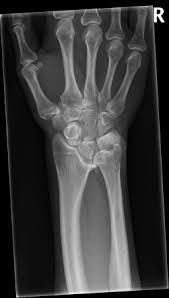

What is Madelung's deformity? Madelung's deformity is a rare arm condition that affects the growth plate of the radius, a bone in the forearm. As a child grows, this abnormal growth results in a misalignment where the two long bones of the forearm (the radius and ulna) meet the bones of the wrist.